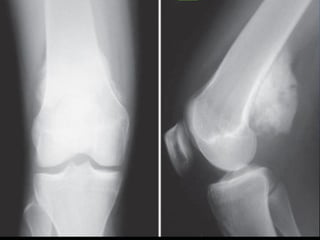

RADIOGRAPH showing typical malignant features including permeative-motheaten

pattern of destruction, irregular cortical destruction and aggressive (interrupted)

periosteal reaction.

Radiological Features

•Plain radiographs are most valuable tool for correct

diagnosis

•Most common is – aggressive lesion in the

metaphysis of long bone(90%).( 10% diaphyseal &

1% epiphyseal)

•Predominantly blastic / lytic

•Lesions are quite permeative & ill defined

•Codman’s triangle, Sunburst / hair on end

appearance may be seen.